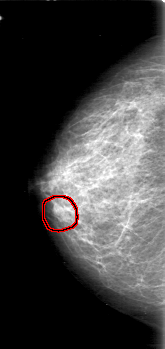

D_4029_1.LEFT_MLO

FILE: D_4029_1.RIGHT_CC.OVERLAY

TOTAL_ABNORMALITIES 1

ABNORMALITY 1

LESION_TYPE MASS SHAPE OVAL MARGINS OBSCURED

ASSESSMENT 0

SUBTLETY 4

PATHOLOGY BENIGN

TOTAL_OUTLINES 1

BOUNDARY